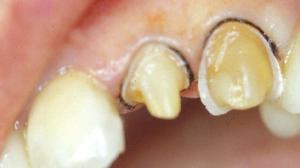

Présentation du cas : Restauration de 22 et 23.

Sur la 22, une préparation coronaire périphérique en vue d'une couronne céramo-céramique a été réalisée.

Une préparation coronaire périphérique a déjà été réalisée sur la 22.